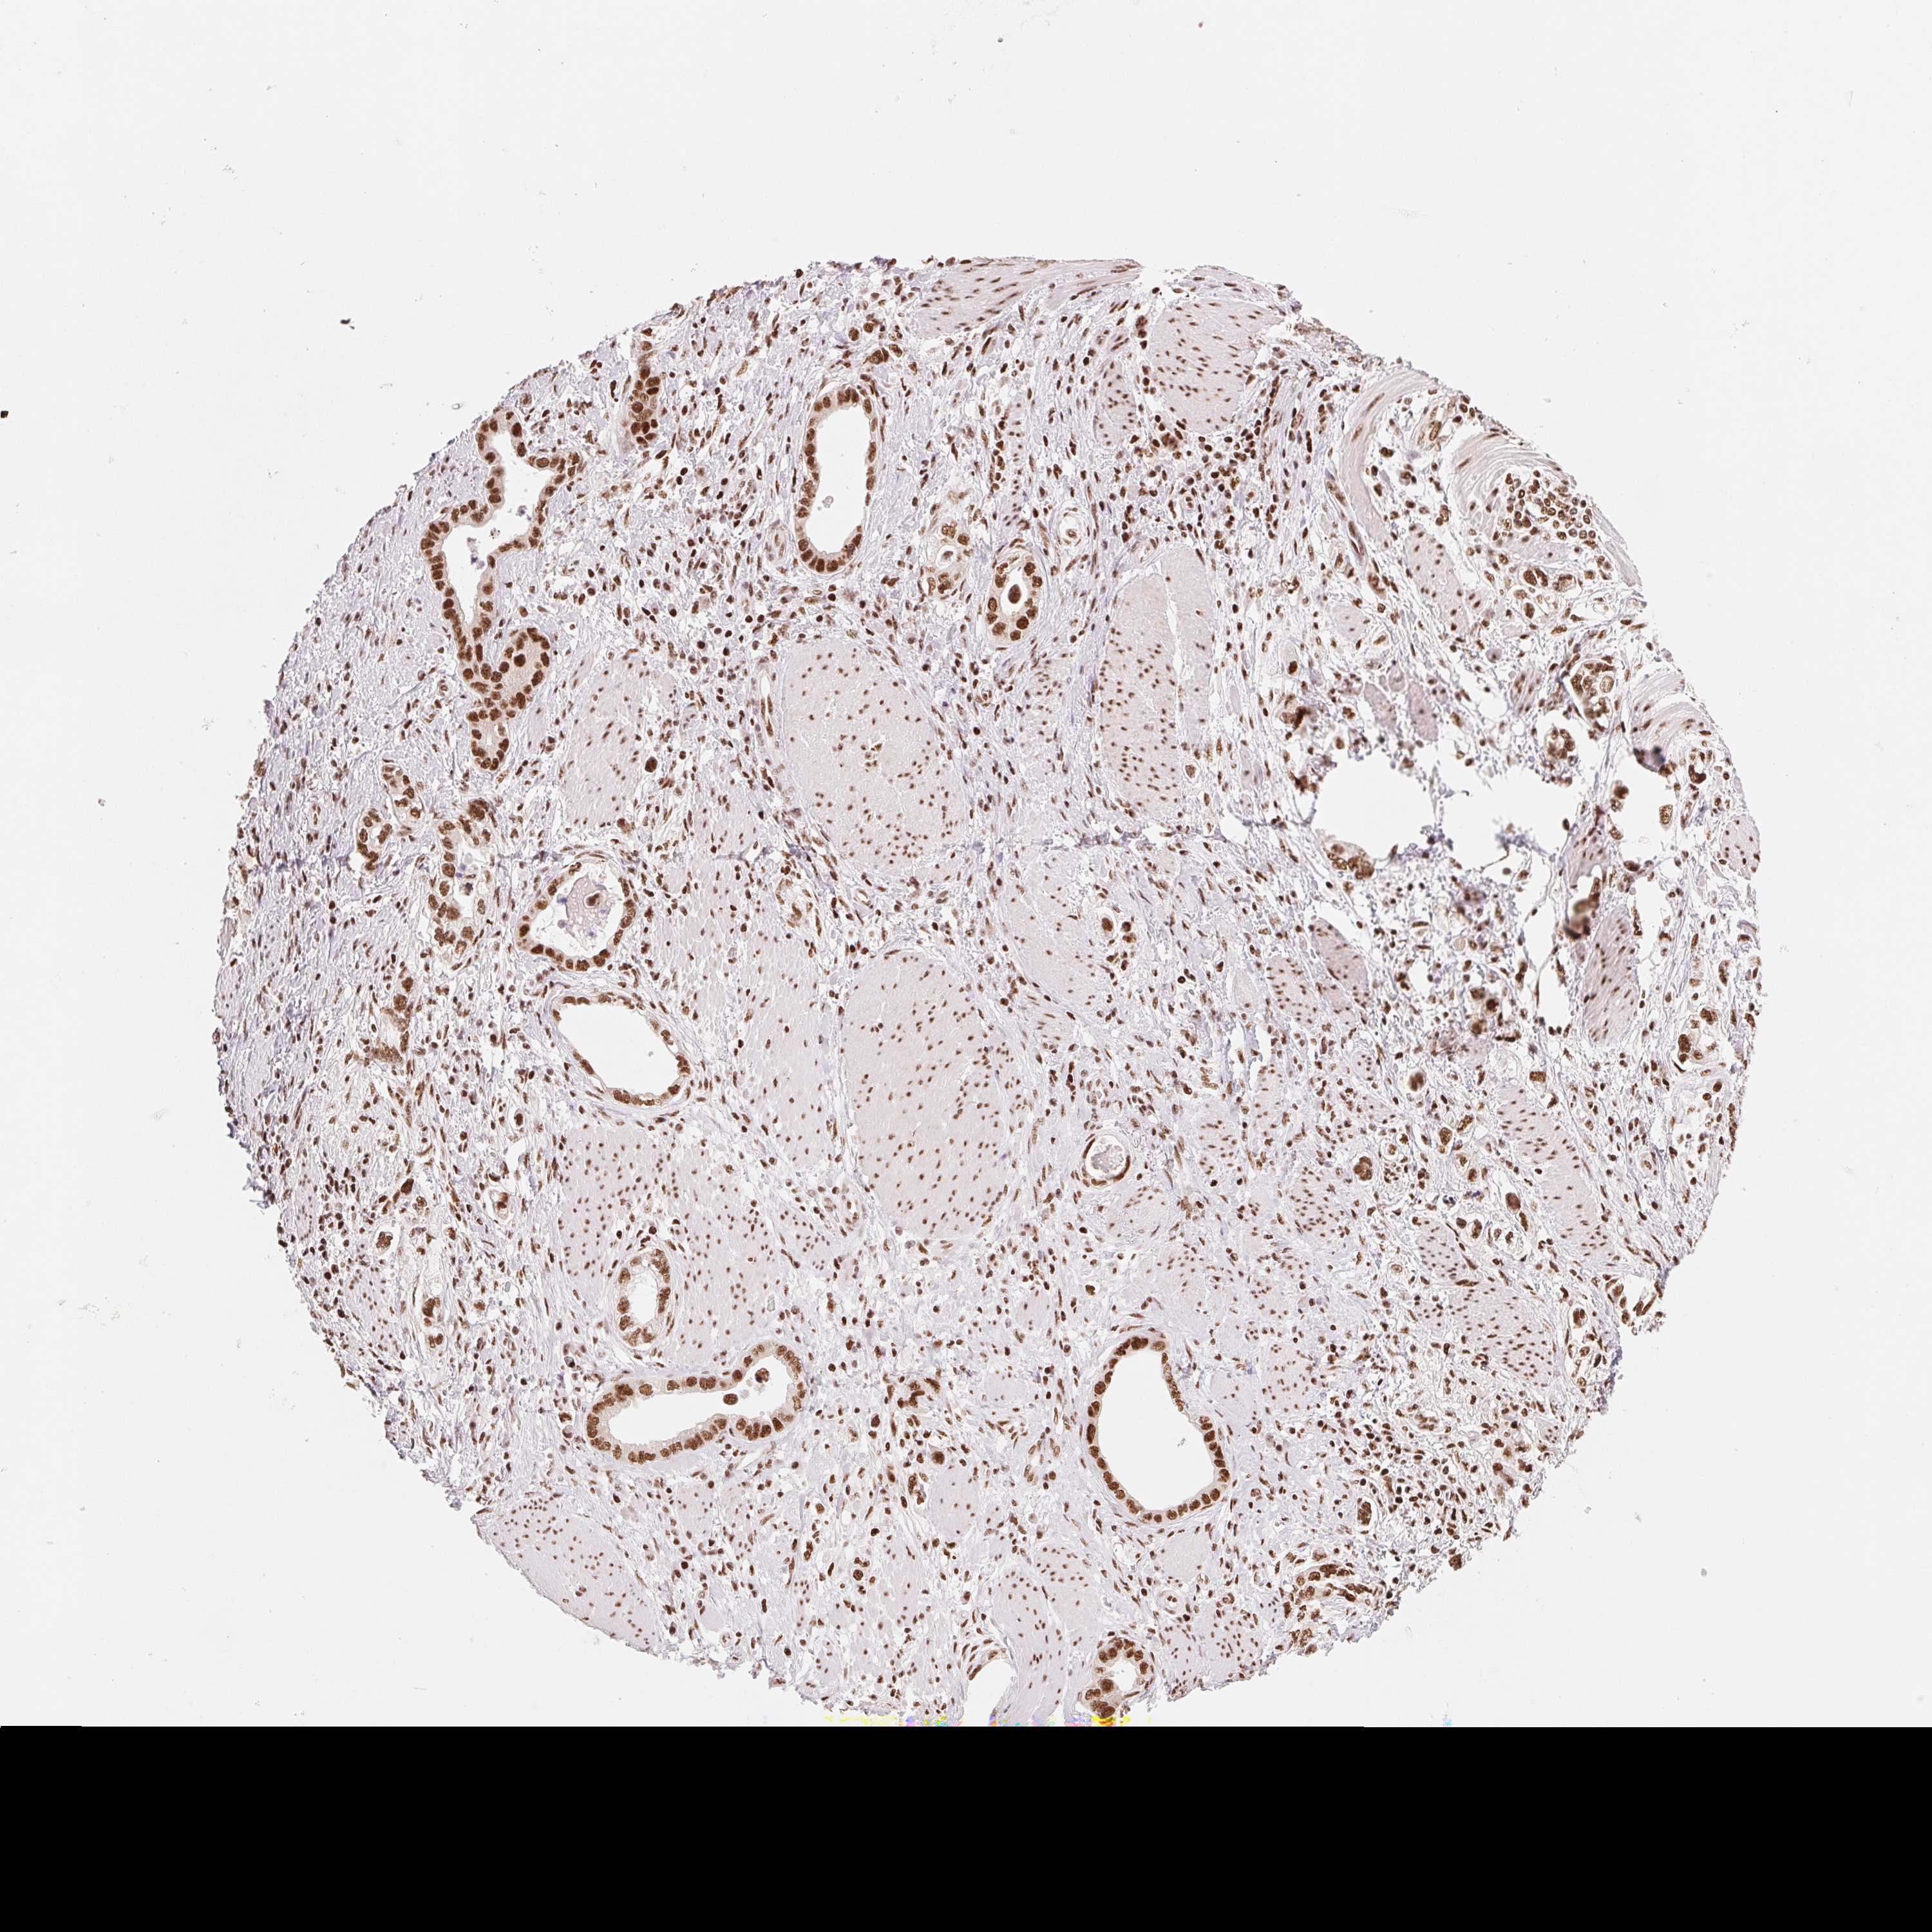

STOMACH CANCER - Protein expressioni

A mouse-over function shows sample information and annotation data. Click on an image to view it in a full screen mode. Samples can be filtered based on level of antibody staining by selecting one or several of the following categories: high, medium, low and not detected. The assay and annotation is described here.

Note that samples used for immunohistochemistry by the Human Protein Atlas do not correspond to samples in the TCGA dataset.

Antibody stainingi

Antibody staining in the annotated cell types in the current human tissue is reported as not detected, low, medium, or high, based on conventional immunohistochemistry profiling in selected tissues. This score is based on the combination of the staining intensity and fraction of stained cells.

Each image is clickable and will lead to virtual microscopy that enables deeper exploration of all samples and also displays staining intensity scores, fraction scores and subcellular localization as well as patient and tissue information for each sample.

Antibody HPA061593

Antibody CAB016327

Staining

High

Medium

Low

Not detected

Intensity

Strong

Moderate

Weak

Negative

Quantity

>75%

75%-25%

<25%

None

Location

Nuclear

Cytoplasmic/membranous

Cytoplasmic/membranous,nuclear

Adenocarcinoma, NOS

Adenocarcinoma, High grade